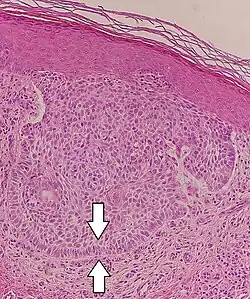

Nodular basal-cell carcinoma (also known as "classic basal-cell carcinoma") accounts for 50% of all BCC.[29] It most commonly occurs on the sun-exposed areas of the head and neck.[30]: 748 [31]: 646 Histopathology shows aggregates of basaloid cells with well-defined borders, showing a peripheral palisading of cells and one or more typical clefts.[29] Such clefts are caused by shrinkage of mucin during tissue fixation and staining.[32] Central necrosis with eosinophilic, granular features may also be present, as well as mucin. The heavy aggregates of mucin determine a cystic structure. Calcification may also be present, especially in long-standing lesions.[29] Mitotic activity is usually not so evident, but a high mitotic rate may be present in more aggressive lesions.[29] Adenoidal BCC can be classified as a variant of NBCC, characterized by basaloid cells with a reticulated configuration extending into the dermis.[29]

Cleft.